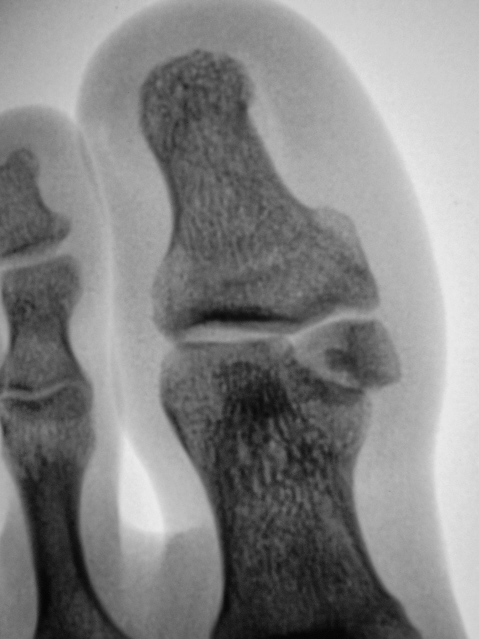

Неконсолидированный перелом головки проксимальной фаланги 1-го пальца?